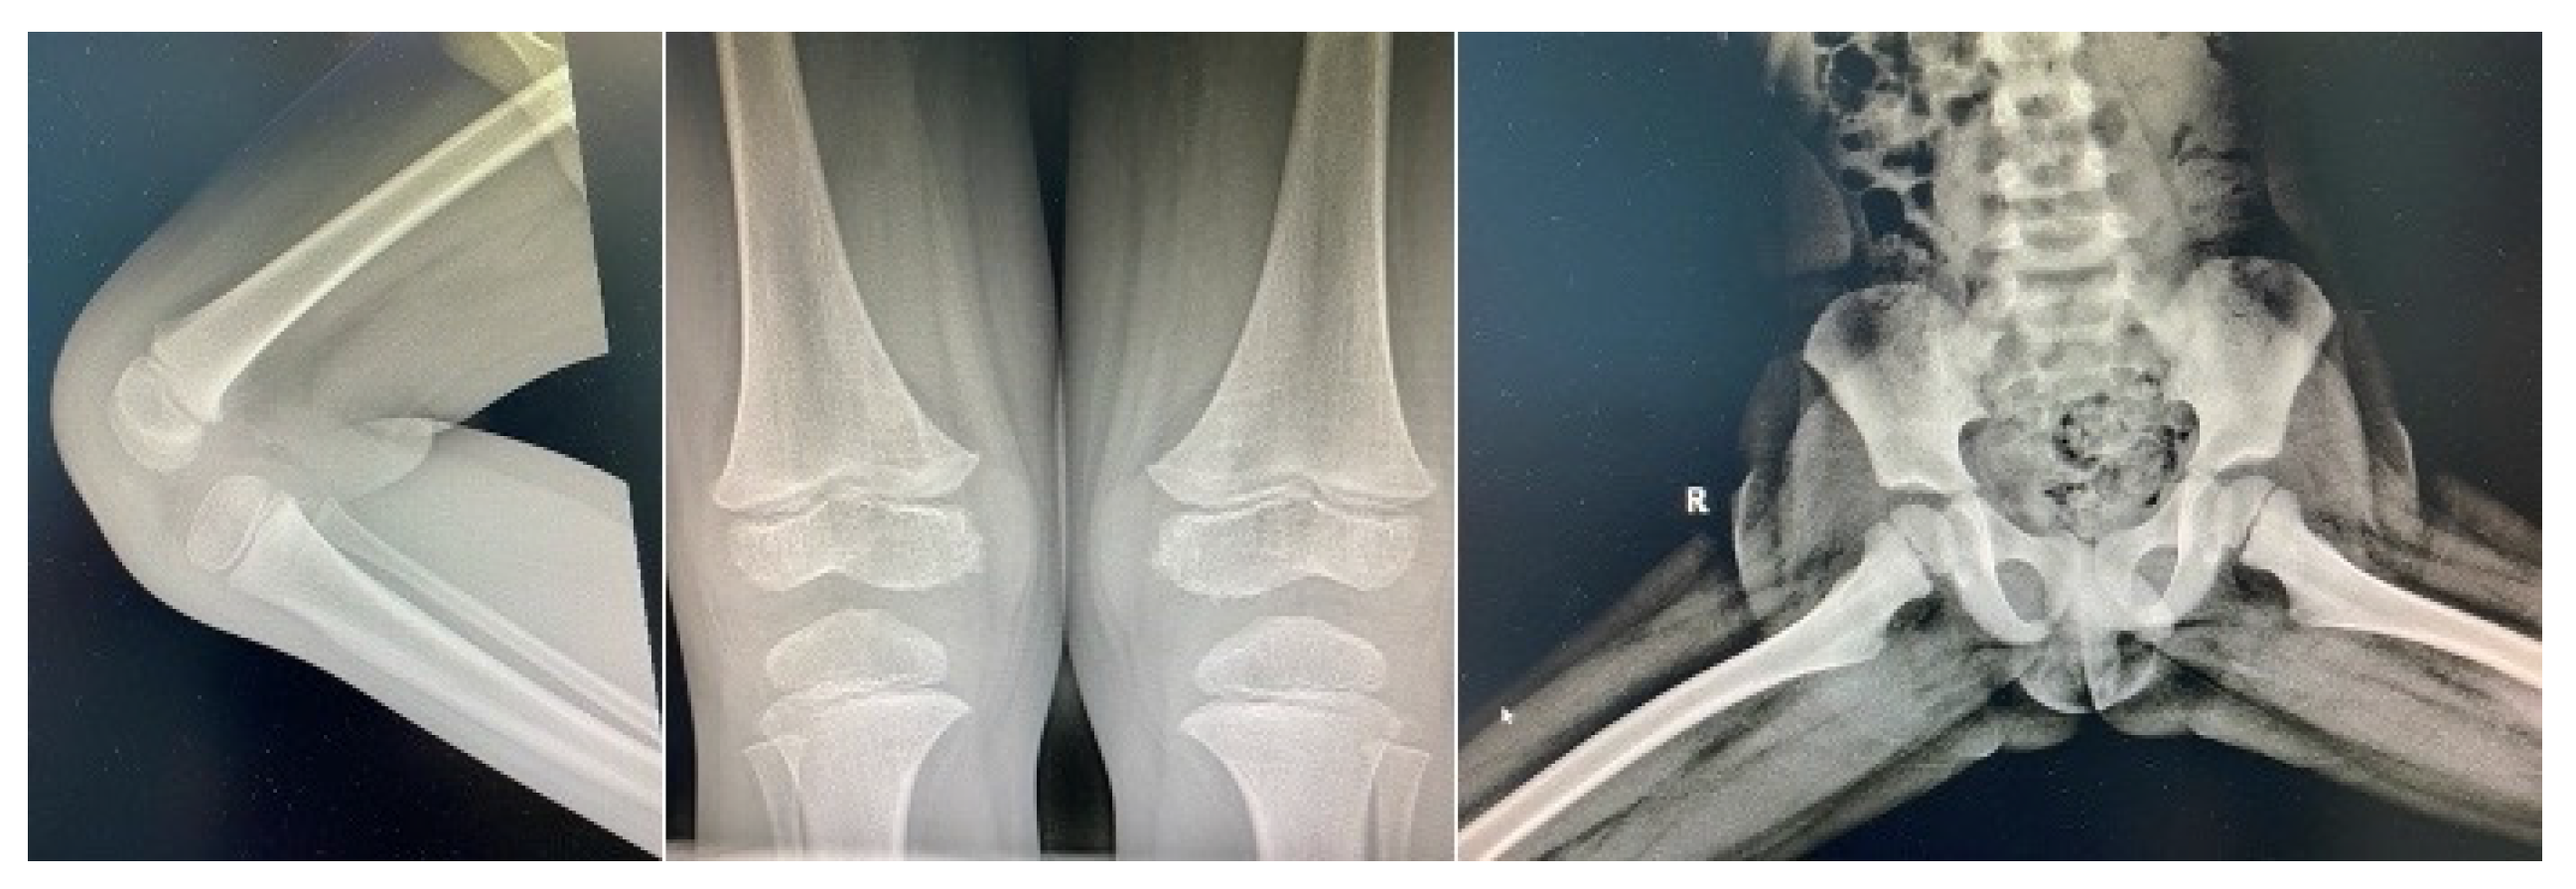

Three weeks later, patient comes back with fever and left knee swelling with partial function impairment, of 24 hours onset. His mother also described, two days prior, non-itching maculo-papular cutaneous rash on chest and belly, which disappeared spontaneously. Clinical examination did not encounter anything out of the ordinary (no fever, no rash), just mild painful swelling of left knee. Laboratory investigations were also, this second time around, in normal range. Borellia infection was excluded. The orthopedic exam did not describe local inflammatory signs, joint mobility and knee X-ray were normal (Figure 3). He received oral anti-inflammatory medication.

Figure 3. Normal bone X-rays.